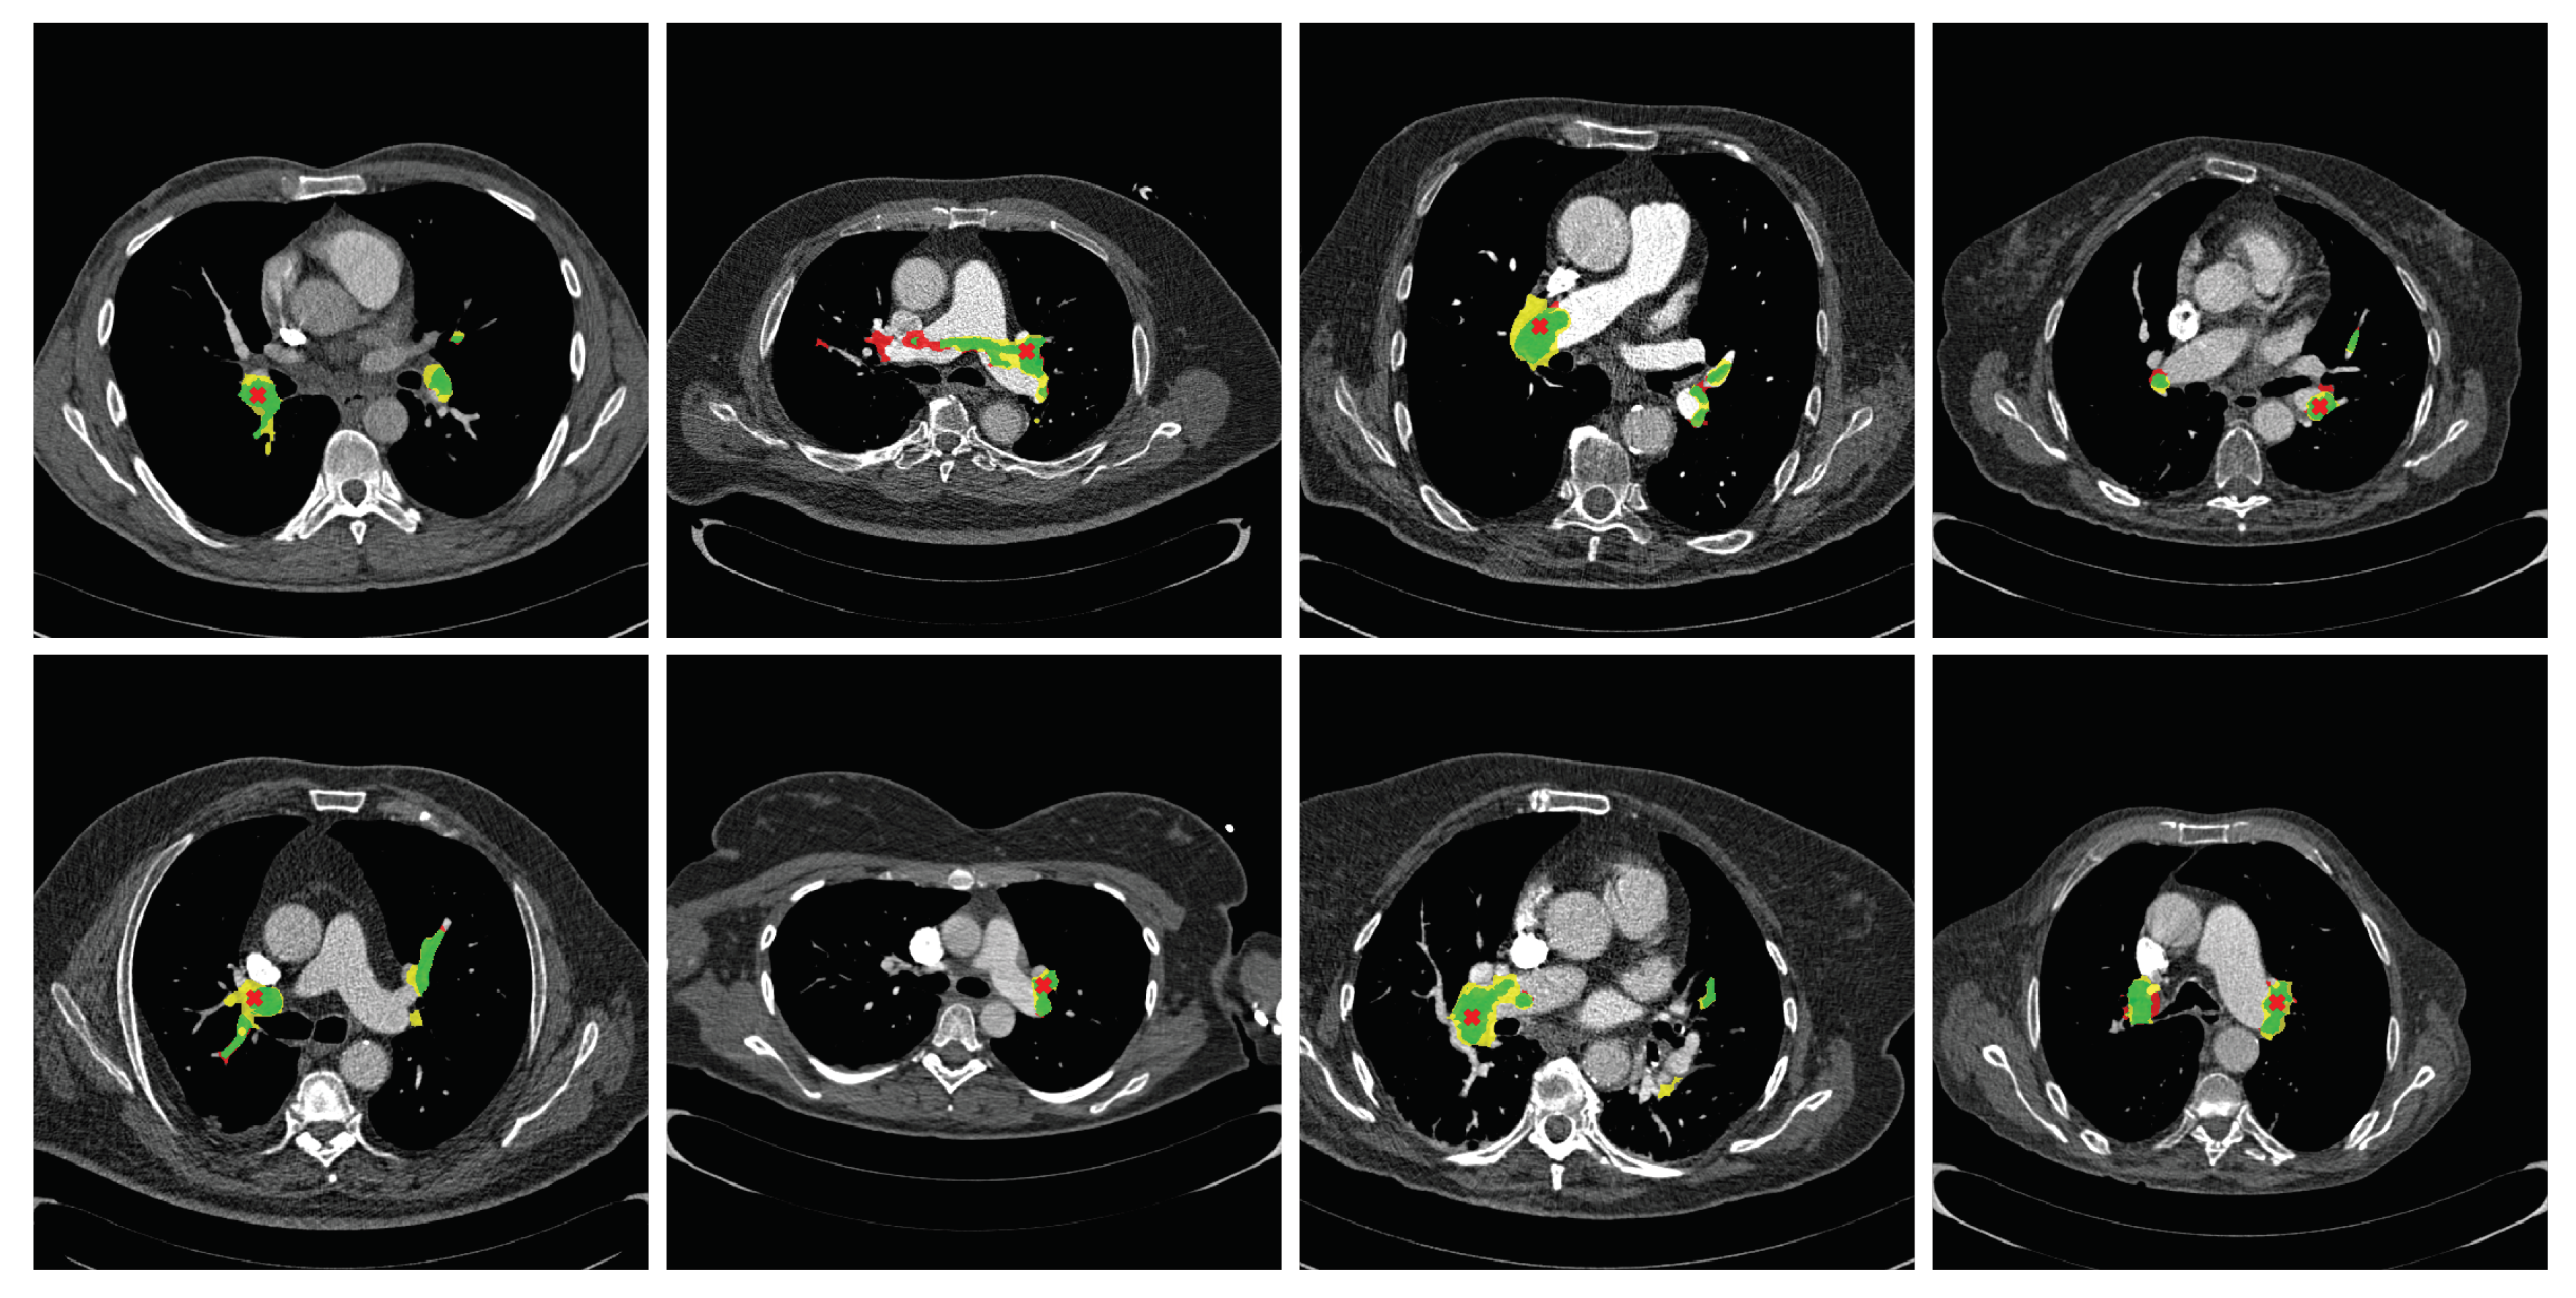

3. Results

First, we evaluated the segmentation performance of the proposed method. Qualitative segmentation results are shown in Figure 3, where green labels represent true positives, red labels false negatives, and yellow labels false positives. The average per-scan segmentation Dice score was 0.485 (standard deviation of 0.297) for the 2 D network, 0.367 (standard deviation of 0.214) for the 2.5 D network, and 0.296 (standard deviation of 0.160) for the 3 D network. In all the cases, the standard deviation showed large discrepancies across scans. Figure A1 shows the relationships between the total size of the emboli in the scan, measured in voxels, and the Dice coefficient. There was a clear trend where the larger was the emboli in the scan, the better was the segmentation.

Figure 3. Network outputs after thresholding and closing operations compared to the reference standard segmentation with ϵ = 0 mm. True positives are shown in green, false positives in yellow, and false negative in red. A predicted clot coordinate for that slice level is represented as a red cross.